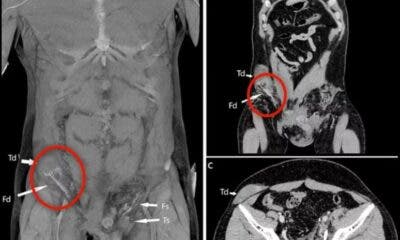

Um italiano teve seu testículo deslocado para o abdômen depois de sofrer um acidente de moto. O caso foi publicado na revista médica BMJ Case Reports...